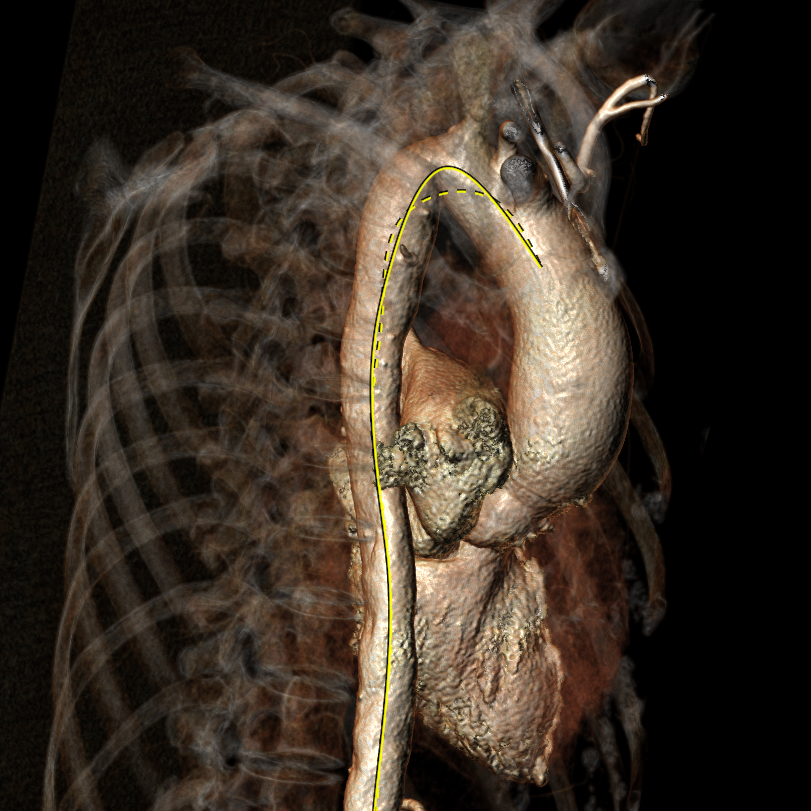

患者17年前因肺结核行左肺叶切除,术前CT结果显示,心脏转位完全偏至左侧胸腔,主动脉弓被挤压成角非常锐利。患者为二叶式主动脉瓣 Type 1型,R-L融合大块钙化脊,且钙化赘生物垂坠至瓣环平面,导致“lazy leaflet”瓣叶结构,主动脉根部极重度钙化,风险度极高,球囊扩张时合并极高的瓣环破裂风险,也可能无法推动钙化使瓣膜形态变形导致严重瓣周漏等并发症。瓣环面积为588.8mm2,平均内径为27.4mm。考虑到患者已行开胸手术,身体虚弱,外科手术风险较高,且介入治疗可更快恢复,减少住院时间,经心脏团队讨论,并与家属协商后,计划行经导管主动脉瓣置换术。

图3. 瓣环和流出道CT面积测量